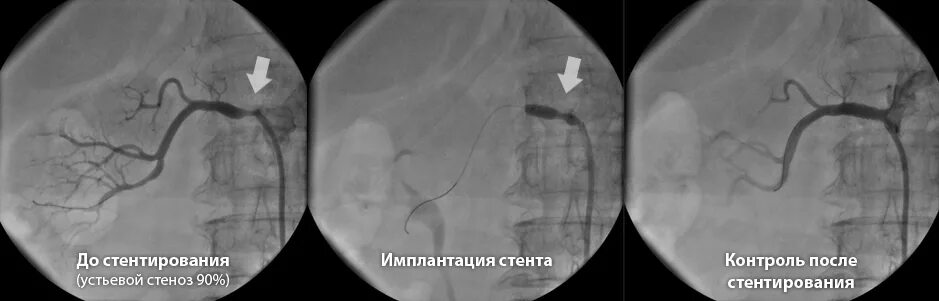

Операция ставят стенд